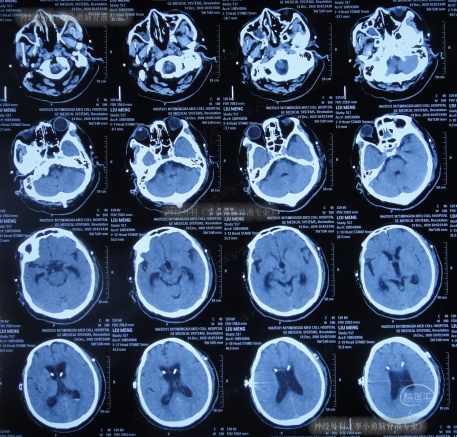

术后次日查头颅CT示脑室有缩小(图-4),意识也有好转。

图-4:2020年12月9日头颅CT